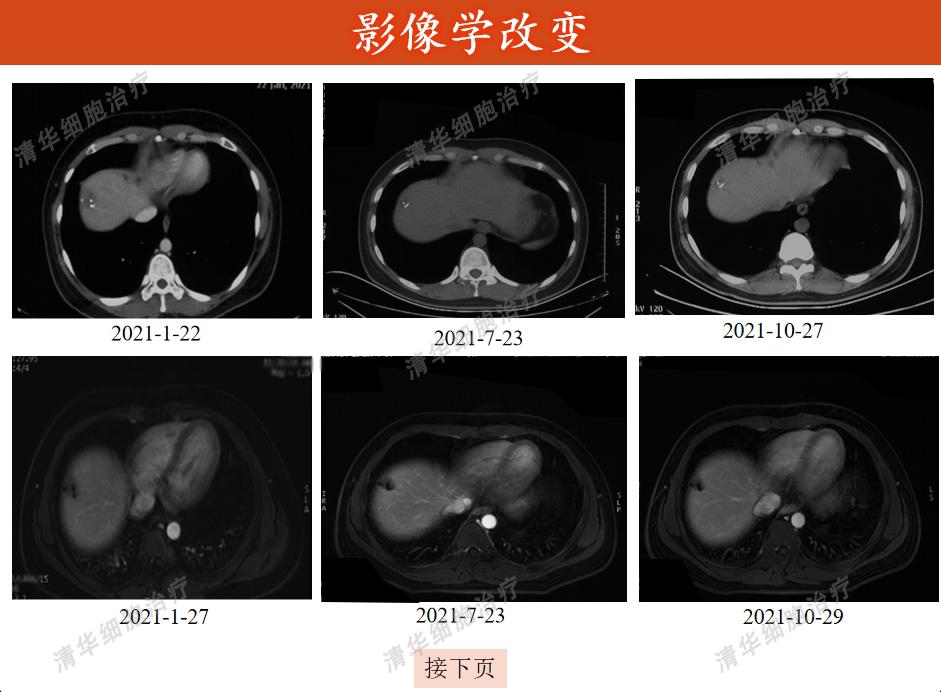

影像方面

杨先生决定于2020年9月采用vNKT细胞免疫治疗,初始方案为1疗程/月,截止2023年3月已完成41个疗程,期间多次复查未见到明显进展征象。